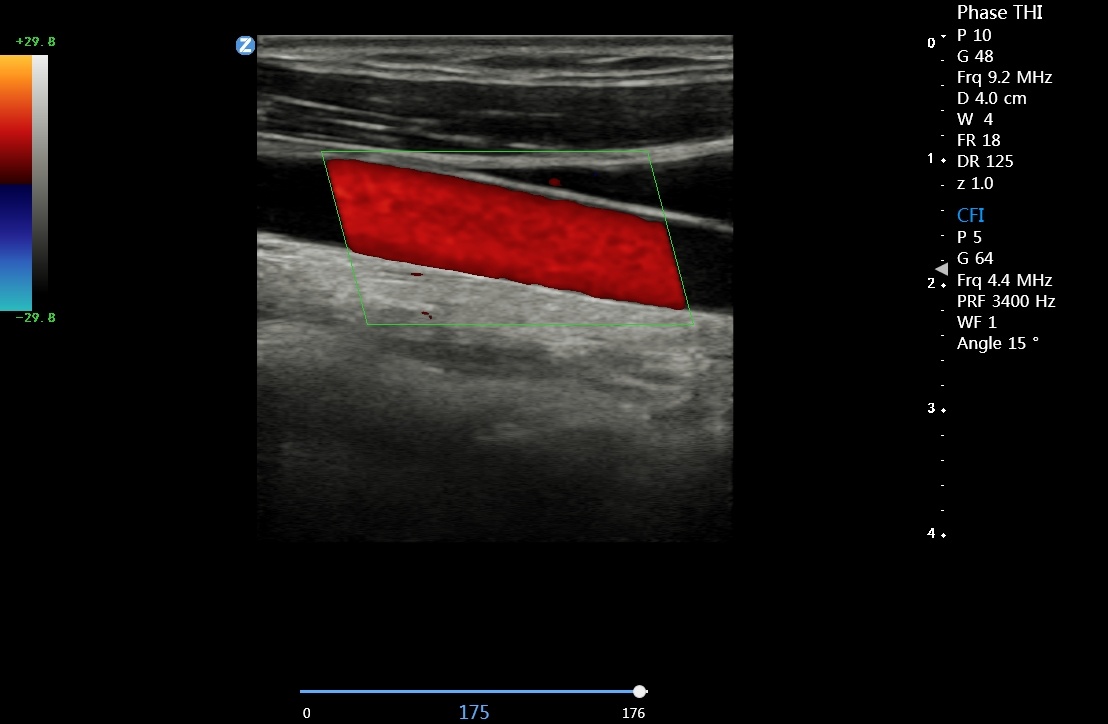

微血流成像 zMicroflow

显著提升肾脏、心肌内膜、淋巴结等组织内部微血管彩色血流信号的显示能力,真实反映血流变化情况

血管内中膜厚度自动测量 IMT

可以自动识别并自动测量血管内中膜的厚度,提供内中膜厚度测量报告,为心脑血管事件的预防提供评估指标